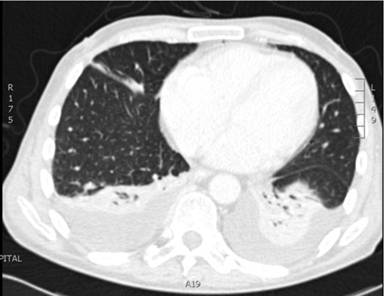

In addition to the multiple pulmonary nodules seen on CT, bilateral lower lobe collapse associated with plural effusions was identified (Figure 1). This was investigated by the respiratory physicians and was managed conservatively in the first instance as the patient was asymptomatic. A repeat CT scan six weeks later demonstrated that both the areas of lower lobe collapse and effusion and pulmonary nodules had resolved spontaneously. This raised questions over the presumptive diagnosis of metastatic pancreatic carcinoma.

Figure 1. Pulmonary nodules on computerised tomography. |